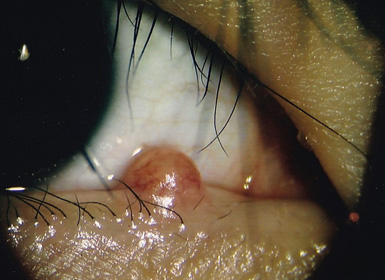

手術前(下の瞼に腫瘍が認められます)

手術後(腫瘍を切除し、傷跡は分かりません)

手術前(瞼の縁にできた腫瘍です)

手術後(腫瘍を切除し、傷跡も綺麗です)